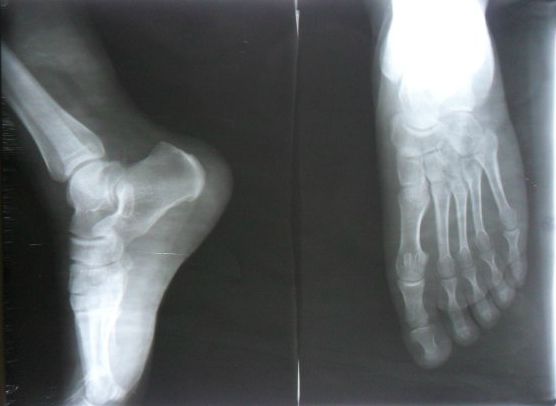

小泽的爸妈赶紧带孩子去医院做了个全身体检,找大夫问孩子为什么不长个了,怎么比爸爸个子还矮?医生看到他们慌慌张张的样子,拿着拍的片子无奈摇头。

原来,正是因为小泽的爸妈给他长期"大补特补",导致孩子营养过剩,骨缝线过早闭合,身体是不会再长高了。